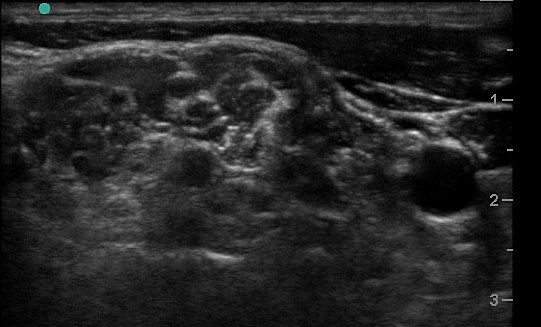

- The interscalene space is between these 2 scalene muscles and contains the brachial plexus

- Visualize the brachial plexus here as a stack of circles with hypoechoic centers

- The plexus will look more echogenic, bundled and honeycombed in the caudal interscalene space

- The brachial plexus is seen immediately adjacent to the superior-posterior border of the subclavian artery as a grouping of small hyperechoic circles with hypoechoic centers, similar to a cluster of grapes.

- Backtrack from this site to the interscalene space by sliding the probe cephalad while keeping the plexus in the center of the image.

- The plexus will change conformation and become more hypoechoic as you slide superiorly.